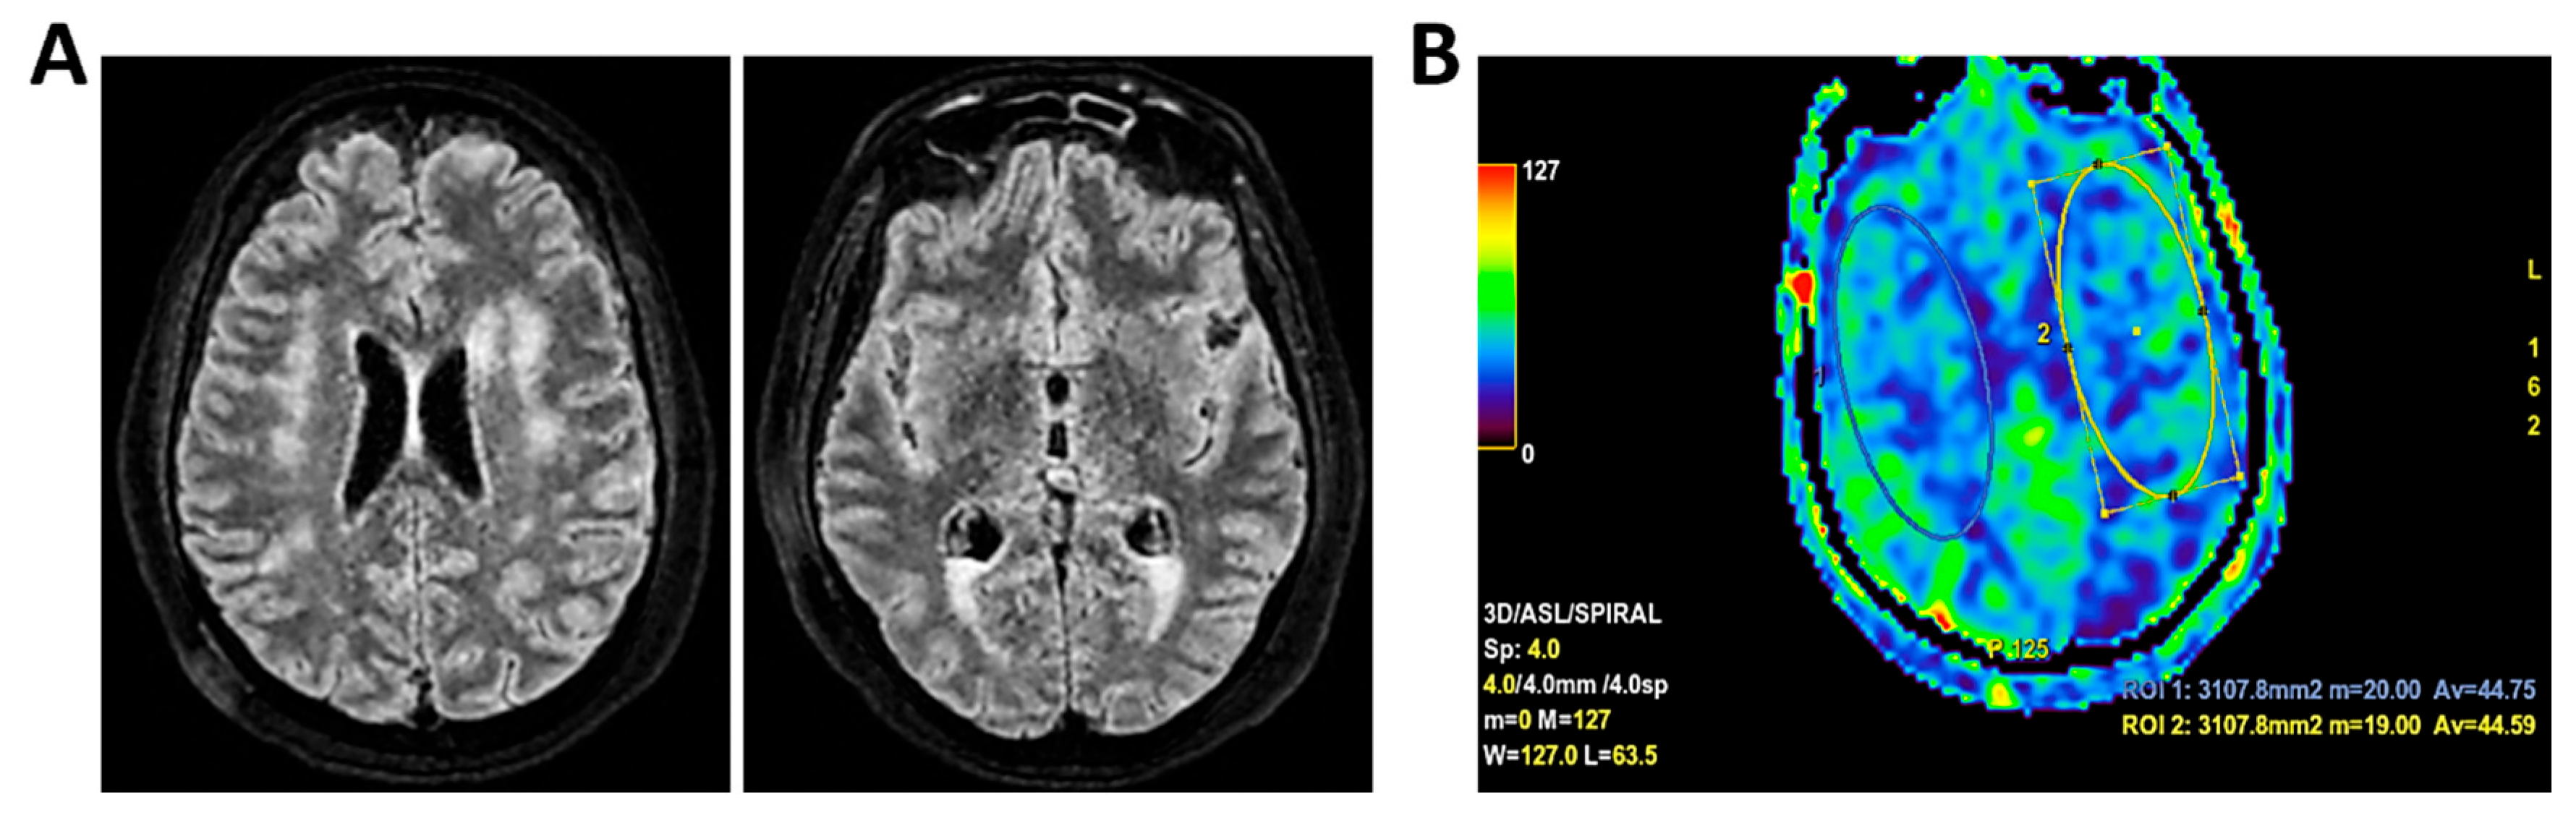

Figure 10.

MRI of patient 5 group 2. A 67-year-old woman with schizophrenia presented to the ER with lethargy and vomiting, following 10 days of fever and dry cough treated ineffectively with Medrol and Cefditoren. Brain CT showed a left temporoparietal hypodensity (sequela) and supratentorial ventricular dilation without midline shift. The lumbar puncture was positive for Listeria monocytogenes (FilmArray). Due to neurological deterioration (GCS 7), she was transferred to the ICU. On day 2, TCCD showed PI values of 1.65 (right) and 1.89 (left), indicating increased cerebral vascular resistance without clear signs of intracranial hypertension. (A) 3D axial FLAIR shows marked and diffuse atrophy of the brain tissue, more pronounced in the left hemisphere where some areas of enlargement of the cerebrospinal fluid spaces are observed, more prominent in the parietal region, and diffuse dilation of the supraventricular system, particularly in the occipital horns. (B) Perfusion study reveals minimal asymmetry in cerebral perfusion values sampled at the level of the semioval centers. Blue circles indicate the ROI used for quantitative CBF analysis.